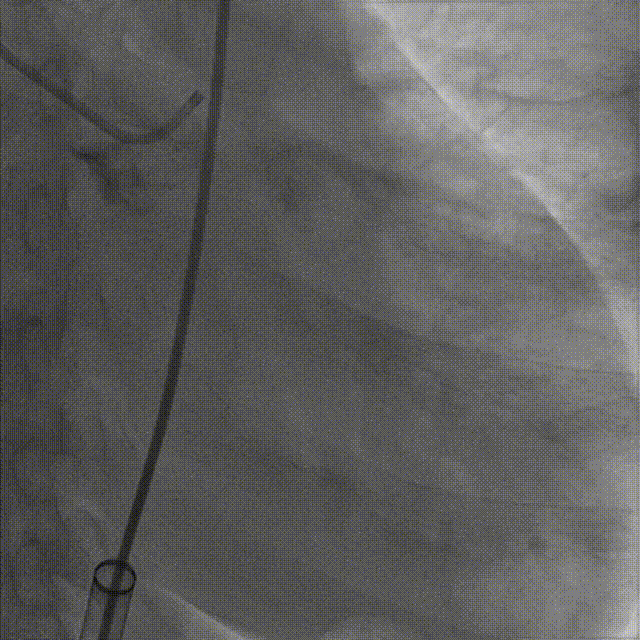

3.20mm球囊预扩,轻微腰征,冠脉显影良好,无造影剂渗漏

20mm球囊预扩